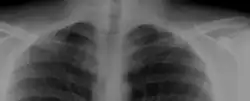

A cervical rib in humans is an extra rib which arises from the seventh cervical vertebra. Their presence is a congenital abnormality located above the normal first rib. A cervical rib is estimated to occur in 0.2%[7] to 0.5%[8] (1 in 200 to 500) of the population.[9] People may have a cervical rib on the right, left or both sides.[10][11]

Most cases of cervical ribs are not clinically relevant and do not have symptoms;[12][13] cervical ribs are generally discovered incidentally, most often during x-rays and CT scans.[8][9][11] However, they vary widely in size and shape,[8] and in rare cases, they may cause problems such as contributing to thoracic outlet syndrome,[12] because they press on the nerves.[12][14]